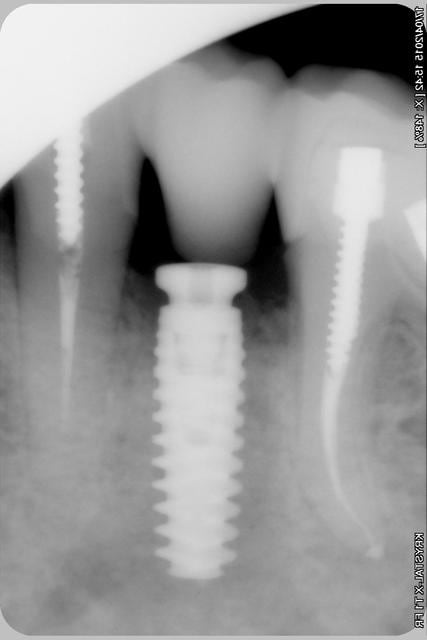

Nouveau patient, pose d'un implant il y a 2 mois....échec sans raisons particulières, douleurs et dépose.

Ce matin repose d'un nouvel implant et comme je ne veux pas prendre de risque, et que les dents adjacentes doivent être couronnées, je pose un bridge en emax press, mais scellé au ciment provisoire...

Si l'implant va bien le bridge sera déposé, coupé, et 44/46 seront collées définitivement après traitement acide et silane.

Si par hasard l'implant pose problème, dépose et bridge collé.

alors là pas du tout, le patient vient me voir pour des implants, donc je fais une étude du cas absence des molaires supérieures, couronnes mandibulaires très ancienne 45 racine cassée, 44 dévitalisée mais passablement déchaussée, donc avulsion de 45 et pose d'un implant avant de refaire les couronnes 46/47 et l'ensemble.

Échec implantaire, et oui ça arrive, même dans un cas paraissant simple.

Dépose gratuite bien sur et repose gratuite aussi, le bridge n'est pas facturé non plus, il le sera sous forme de 2 couronnes que cette fois ci l'implant fonctionne ce que j’espère, ou laissé en bridge si l'implant devait être retiré.

Le fait de scellé au ciment temporaire ne pose en principe pas de problème pour 3 à 6 mois.

Oui, un Px, le premier était un Reg.

l'os était tendre, ce qui explique le choix du Px